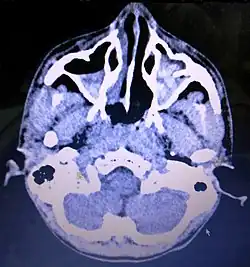

CT Brain showing air-fluid level in bilateral maxillary air sinuses post brain trauma. Maxillary sinusitis will also shows similar air-fluid collection and should be rule out from history taking.

Maxillary sinusitis is inflammation of the maxillary sinuses. The symptoms of sinusitis are headache, usually near the involved sinus, and foul-smelling nasal or pharyngeal discharge, possibly with some systemic signs of infection such as fever and weakness. The skin over the involved sinus can be tender, hot, and even reddened due to the inflammatory process in the area. On radiographs, there is opacification (or cloudiness) of the usually translucent sinus due to retained mucus.[9]